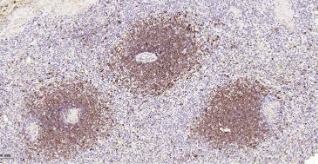

Immunohistochemical analysis of paraffin embedded Human spleen tissue slide using IHC0556H (Human CD22 Kit).